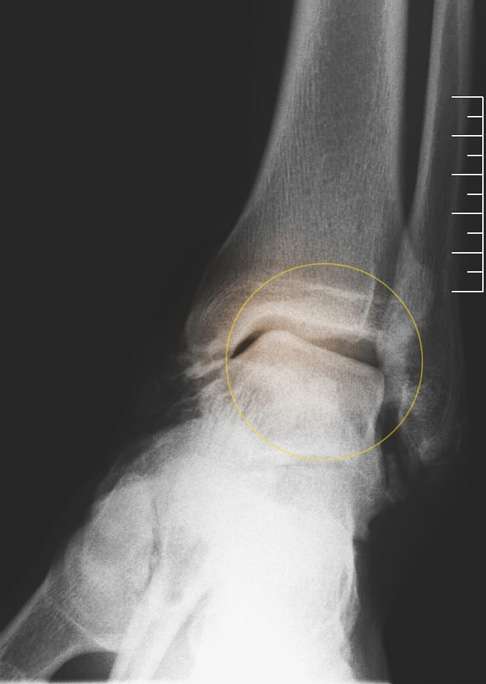

Sprunggelenksimpingement und Sprunggelenksarthrose

Der beim Hohlfuß sehr hochstehende Fußrist (Fußspann) schränkt die Beweglichkeit des Sprunggelenks ein. Vor allem im vorderen Bereich des Sprunggelenks kann der Hohlfuß zu einem Impingement, also einer Bewegungsblockade im Sprunggelenk führen. Dies kann sich zu einer Sprunggelenksarthrose entwickeln.

Ein weiterer schädigender Einfluss auf das Sprunggelenk entsteht durch die Einwärtskippung des Fersenbeines. Der Talus (Sprungbein), der auf dem Fersenbein aufsitzt, steht dann nicht mehr gerade in der Gelenkgabel des Sprunggelenks. Dadurch entstehen knorpelschädigende Überlastungen, die langfristig zur Sprunggelenksarthrose führen.

Bildgebende Diagnostik: Röntgen, DVT, MRT

Auf Röntgenbilder finden wir eindeutige Hinweise auf degenerative Veränderungen von Sprunggelenk und Fußgelenken. Unter Belastung – also im Stehen – können wir zudem eine Fehlstellung des Fersenbeines in mehreren Ebenen auf den Bildern zeigen. Des Weiteren untersuchen wir die Vorfußstellung im Verhältnis zum Rückfuß.